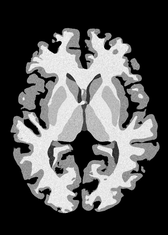

4.2 Registration to a 100 micron ex-vivo brain MRI volume

To showcase the efficacy of our method on real large scale images, we register a 250 in-vivo MRI image (Lüsebrink et al., 2017) to a 100 ex-vivo FLASH human brain volume (Edlow et al., 2019). This represents an inverse problem with more than 11.2B optimizable parameters (compared to 20M for clinical datasets), or 44.8GB of GPU memory. The entire problem does not fit on most GPUs, necessitating distributed multimodal registration. We optimize a composite transform - affine followed by a diffeomorphic mapping; details can be found in Section E.1. Multimodal deformable registration took 58 seconds on 8 NVIDIA A6000 GPUs, which is unprecedented at this resolution. Fig. 6 shows qualitative results, highlighting the ability to register highly detailed structures such as cerebellar white matter; these structures are not visible at macroscopic scales. The resultant advantages of performing registration at this scale can allow researchers to characterize the neuroanatomy at microscopic resolutions and allow morphometric analysis of cortical layers and subcortical nuclei among other structures.